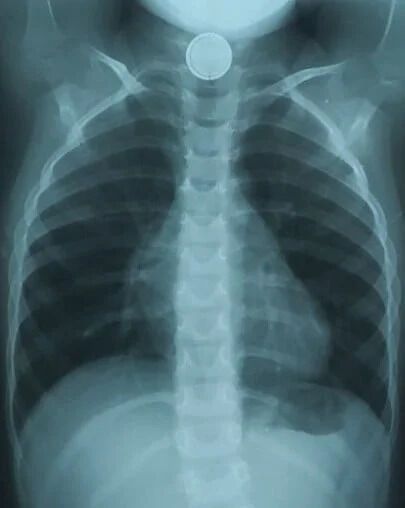

В Днепре трехлетний ребенок проглотил круглую батарейку. Из-за этого малышу понадобилась срочная операция.

Об этом сообщает телеканал D1. Батарейка пробыла в пищеводе малыша полтора часа и успела окислиться.

Медики провели специальные обследования и с помощью эндоскопического вмешательства удалили посторонний предмет.

На четвертый день после операции ребенку провели контрольную эзофагоскопию – осмотрели внутреннюю поверхность пищевода. На месте, где была батарейка, у маленького пациента обнаружили дефект слизистой – элемент электропитания повредил пищевод.